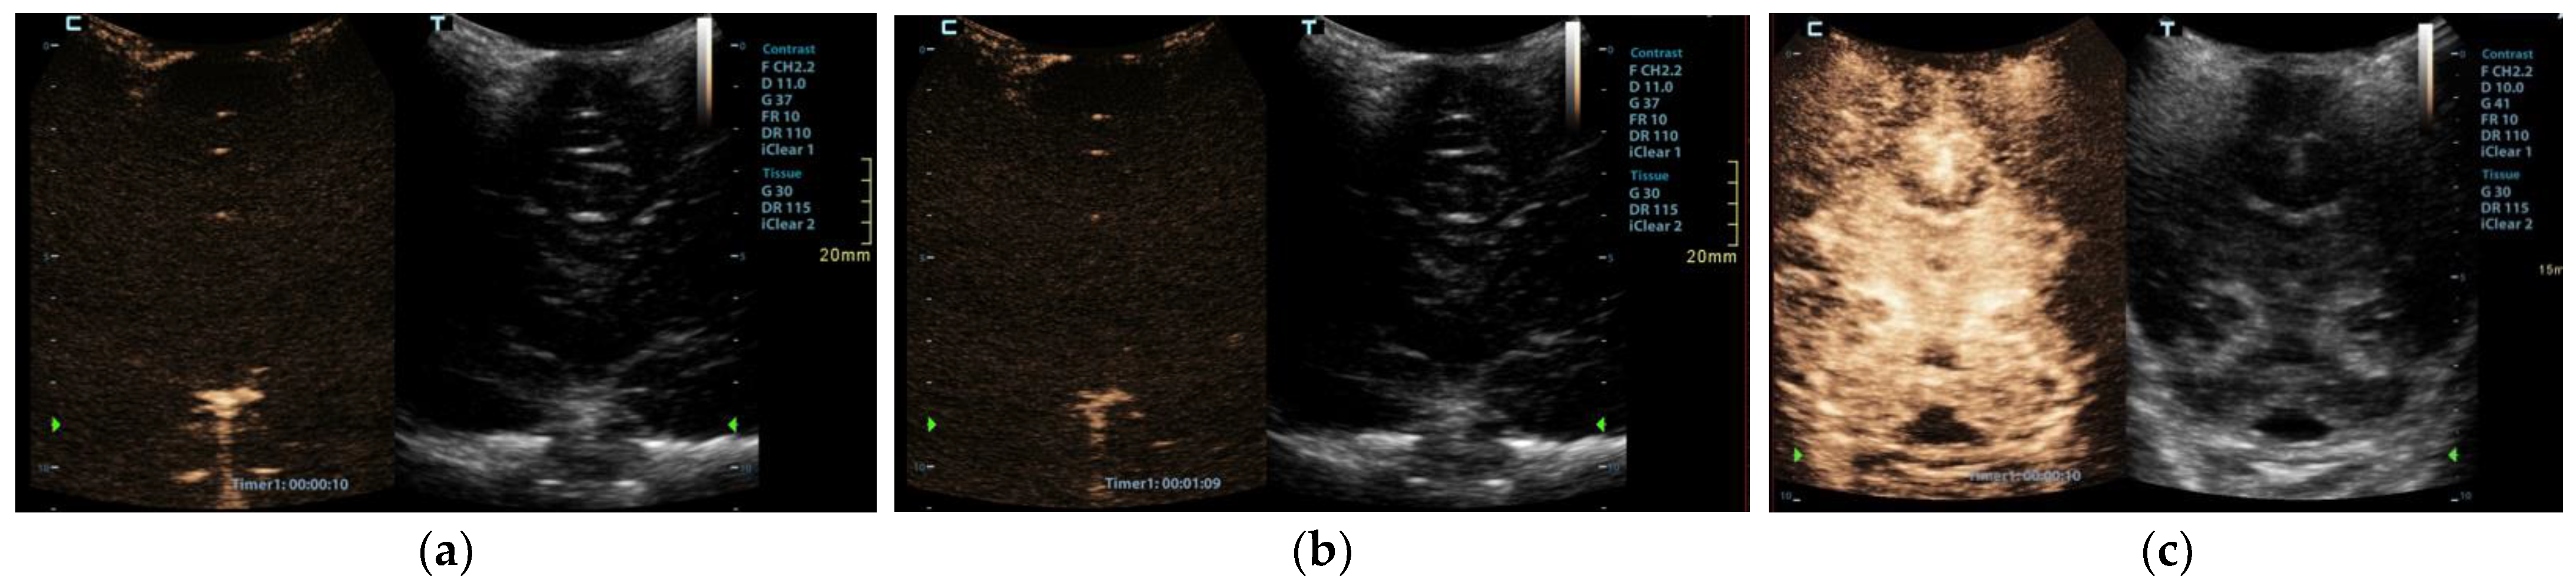

CEUS was performed as an ancillary imaging test for the confirmation of brain death. Before the examination, the details of the examination and the risks for the patient were explained to the child’s guardian. Written informed consent was obtained from the child’s guardian to perform the brain CEUS scan. The examination was performed by a paediatric radiologist with 2 years of subspecialty experience in paediatric brain imaging and 4 years of experience in performing CEUS examinations. For the examination, a Mindray M9 ultrasound scanner with a 1.4–5.1 MHz convex ultrasound transducer was used (Mindray, Shenzhen, China). SonoVue (Bracco, Milan, Italy) was used as the contrast agent. The anterior fontanelle was used as the acoustic window to scan the brain in the coronal and sagittal planes. Firstly, pre-contrast grey-scale imaging was performed to optimise the image. After that, a contrast-specific imaging mode and a low dynamic mechanical index (MI) of 0.06–0.07 was used for the scanning during the CEUS examination. To enable the simultaneous attachment of the US contrast agent and saline to the line, to avoid any delays in flushing the line with a saline flush, a three-way stopcock was connected to the existing peripheral intravenous line. At the start of the examination, 0.3 mL of US contrast agent, followed by a saline flush, was intravenously applied through a peripheral line. Only one bolus of US contrast agent was administered during the examination. For the first 60 s after the contrast administration, a continuous cine clip was obtained in the coronal plane at the level of the third ventricle, including the frontal horns of the lateral ventricles and heads of the caudate nuclei bilaterally. After that, intermittent images were obtained during the next 10 min in order to assess brain perfusion and avoid excessive contrast microbubble destruction from continuous imaging. The CEUS examination showed enhancement of the extracranial vessels and a lack of enhancement of the intracranial vessels (Figure 2). Only a scant amount of contrast microbubbles was observed within the left middle cerebral artery and pericallosal artery during the examination (Figure 3). After 10 min, we observed complete microbubble clearance and finished with the examination. The brain CEUS examination was performed in a paediatric intensive care unit at the bedside, and the whole procedure, including preparation, lasted approximately 15 min. No adverse effects were observed after the intravenous application of US contrast agent.

Figure 2. Midcoronal contrast-enhanced ultrasound images of a 1-year-old infant’s brain obtained (a) 10 s and (b) 69 s after the contrast administration. Both images demonstrate a lack of enhancement of the intracranial vasculature and no brain perfusion. (c) Normal CEUS brain scan in another infant is shown as a comparison.